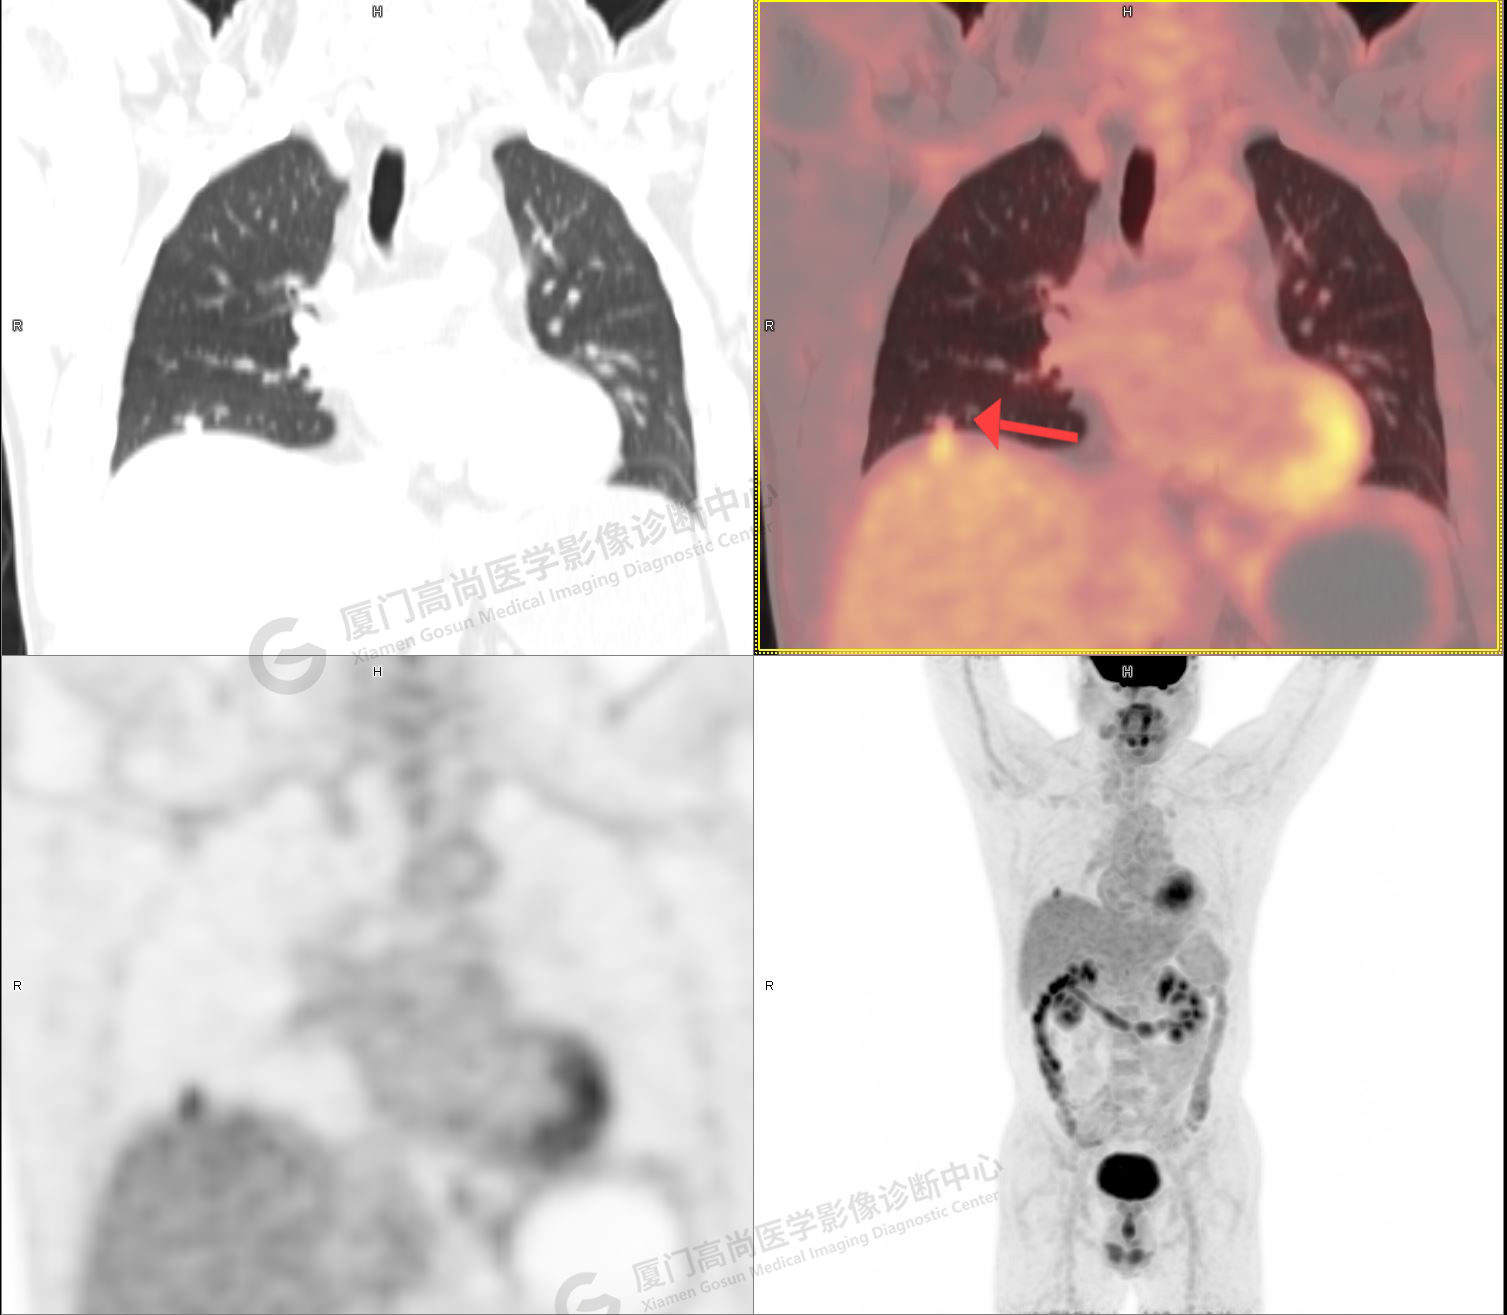

PET/CT影像圖

圖1

圖2

PET/CT示:右肺下葉結(jié)節(jié),代謝增高,考慮為周圍型肺癌,建議穿刺活檢。

病理證實(shí)是肺腺癌。